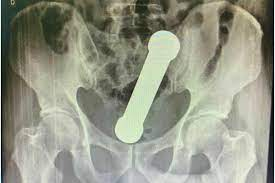

Segundo o relatório, o homem, cuja identidade foi preservada por razões éticas, deu entrada em uma unidade hospitalar com dores abdominais intensas e desconforto prolongado. Após exames de imagem, foi detectado um objeto metálico retido na região retal. Tratava-se de um halter cilíndrico, normalmente utilizado para musculação, com aproximadamente 20 centímetros de comprimento e 4 centímetros de largura.

Os profissionais envolvidos no atendimento destacaram a complexidade do caso. A retirada de objetos retais é uma ocorrência conhecida na medicina de emergência, porém o peso e o formato específico do halter representavam um risco significativo, especialmente para perfuração intestinal e hemorragias internas. O artigo detalha o uso de técnicas específicas de sedação, manobras abdominais e instrumentos cirúrgicos minimamente invasivos para realizar a remoção sem a necessidade de cirurgia aberta.